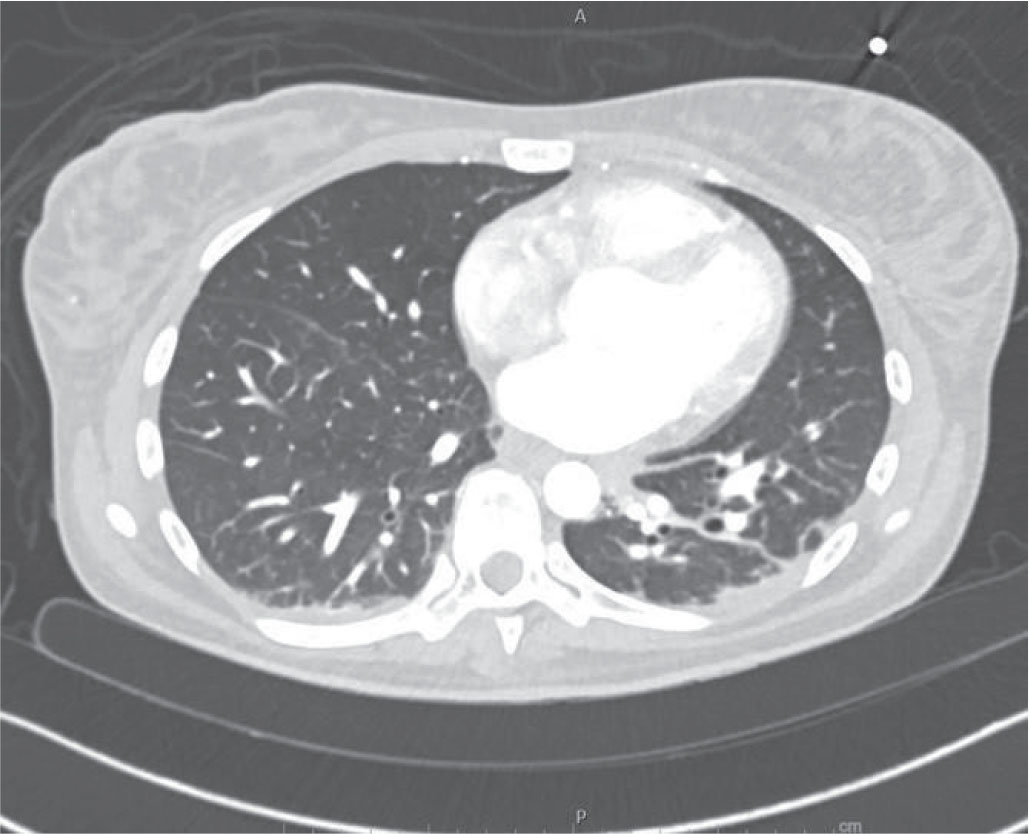

Pulmonary CT showed massive pulmonary infiltrates with pleural and pericardial effusion (Fig. 1), and sputum was positive for E. coli, E. gallinarum, and Influenza A virus. ECG and troponin levels excluded acute coronary syndrome. Non-invasive ventilation and directed antimicrobial therapy were promptly started, and a session of continuous venovenous hemofiltration in combination with CytoSorb led to clinical improvement, with reduction of inflammatory markers, normalization of cardiac and pulmonary function, and induction of diuresis.

FIGURE 1 -. Pulmonary CT scan in patient #1 showing pericardial and bilateral pleural effusion and multiple areas of ground-glass type parenchymal consolidation.